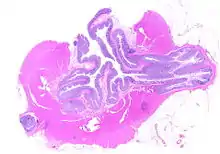

Whole slide of a transverse section of the left colon with diverticulosis

Diverticulosis is defined by the presence of multiple pouches (diverticula) in the colon.[22] In people without symptoms, these are usually found incidentally during other investigations.